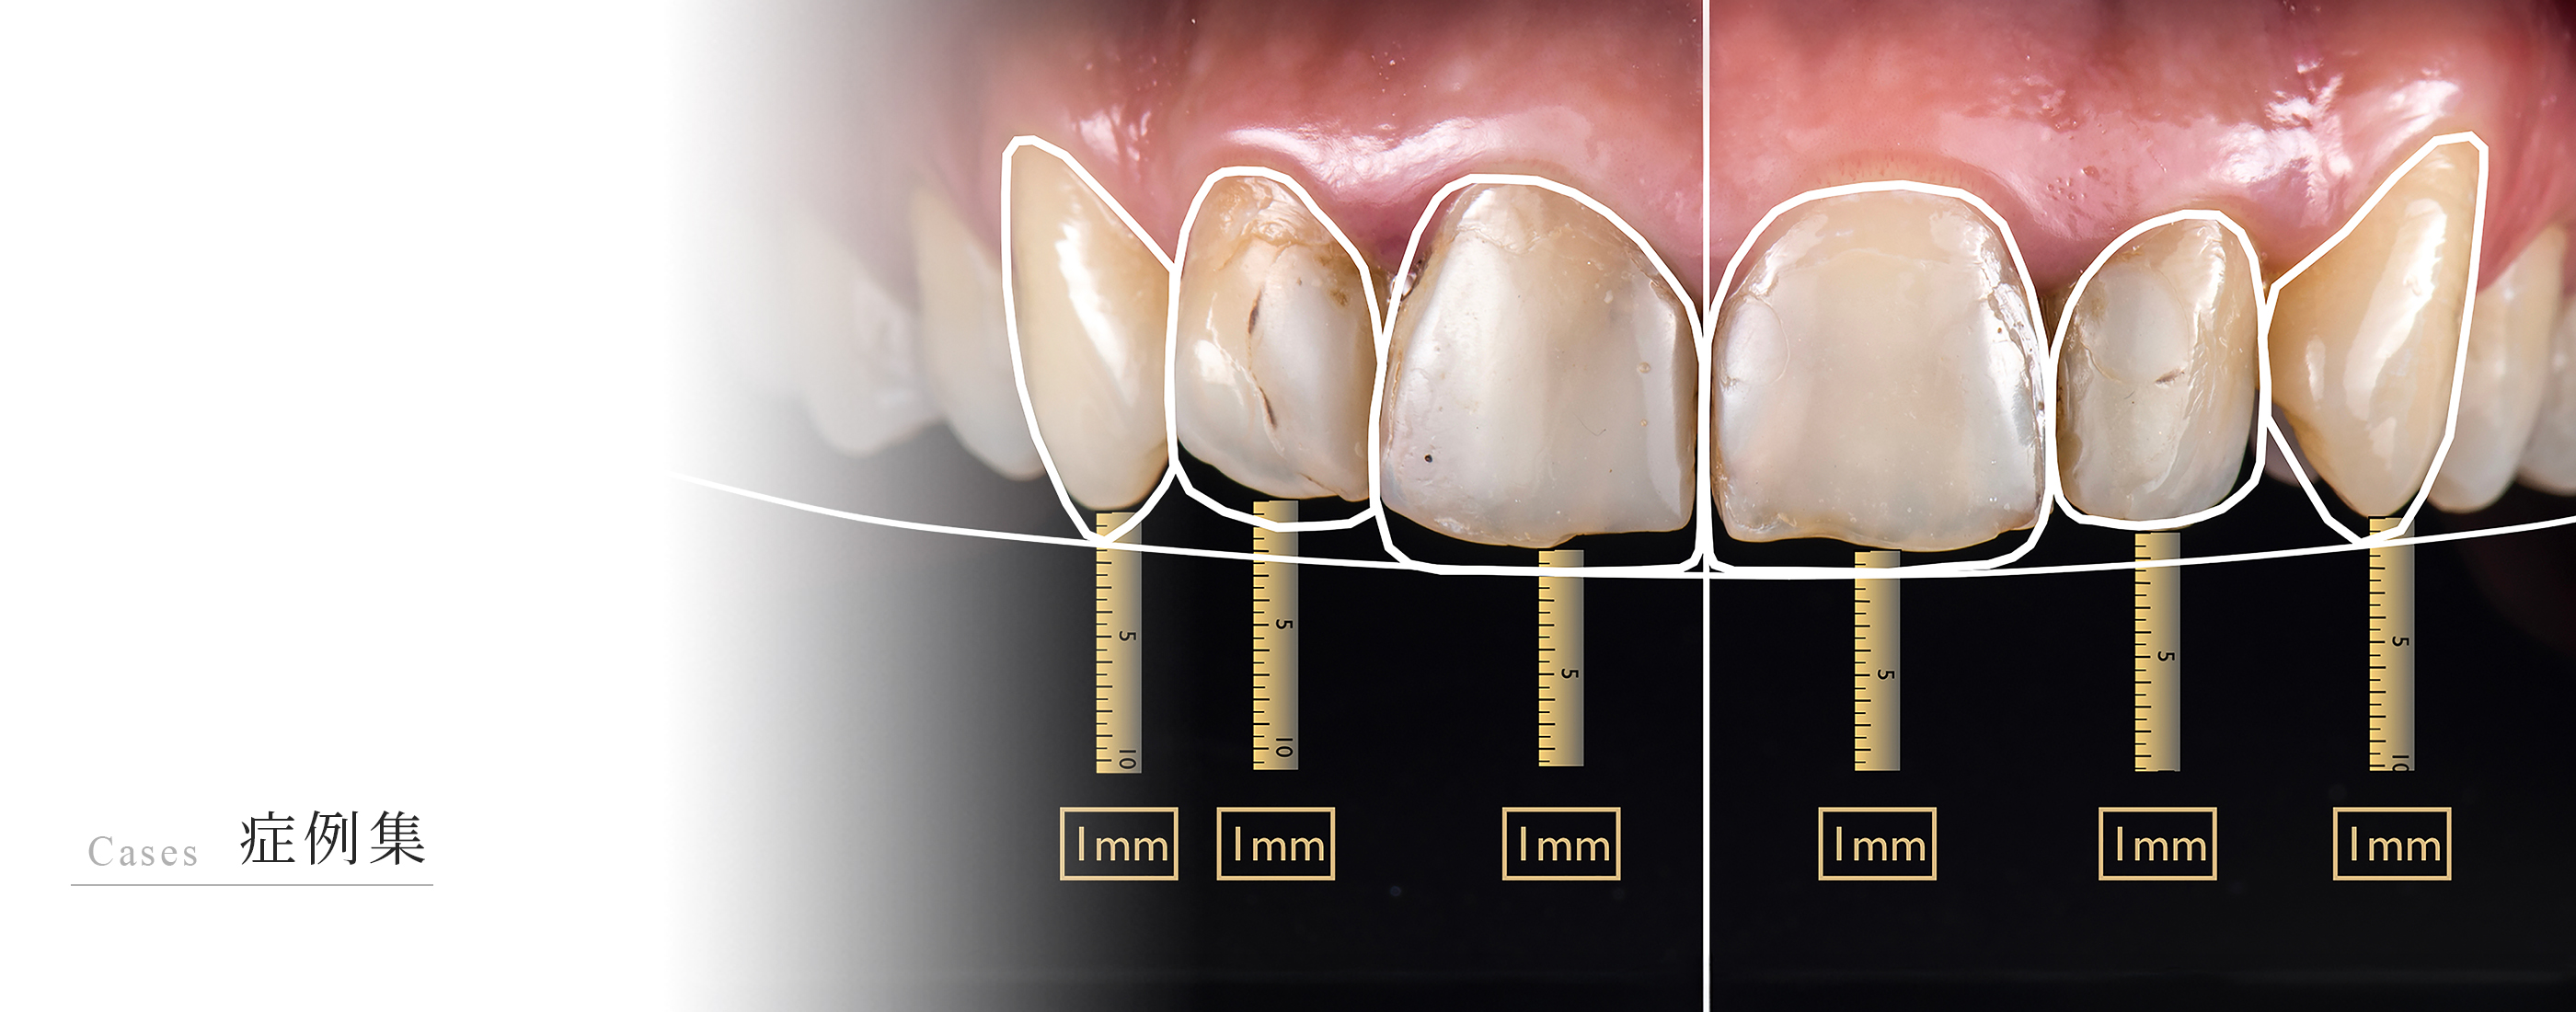

ブリッジの支台になっている上顎側切歯に大きな膿がみられ、この歯を残せなければ無傷の隣の犬歯を削ってブリッジの支台にしなければいけないケースです。できれば、上顎側切歯の膿を治して再度ブリッジの支台として使いたいので、精密再根管治療を行うことになりました。 上顎側切歯の冠状断のCT画像です。 側切歯の根…